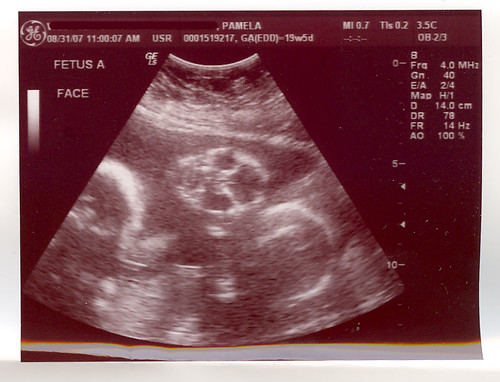

A: